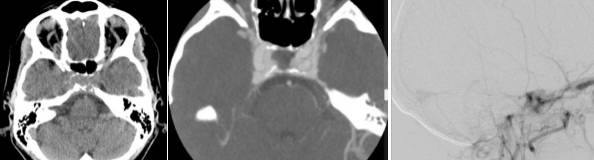

女,60岁,眶后头痛2月,视力下降伴复视4天。

脑寄生虫病、低灌注脑梗死、基底动脉尖综合征丨3分钟读片 ...

答案:颈内动脉-海绵窦瘘。狭义的颈内动脉海绵窦瘘(CCF)通常指的是颈内动脉海绵窦段的动脉壁或其分支发生破裂,以致与海绵窦之间形成异常的动静脉交通,而广义的CCF还包括海绵窦的硬脑膜动静脉瘘。Barrow等在1985提出了广义的CCF分型,分别为:A型,颈内动脉直接与海绵窦相交通;B型,颈内动脉分支与海绵窦相交通;C型颈外动脉分支与海绵窦相交通;D型即B+C,颈内和颈外动脉都通过其脑膜支与海绵窦相通,常有双侧同时供血。临床工作中,由于治疗理念和方法上存在区别,目前通常将BarrowA型单列为CCF,又称直接型颈动脉海绵窦瘘(狭义CCF),而B、C和D型统称为海绵窦硬脑膜动静脉瘘。CCF可分为外伤性和自发性。外伤性CCF较为常见,通常见于交通事故中伴有颅底骨折的外伤患者,颞骨和蝶骨的骨折碎片刺破海绵窦段颈内动脉壁,骨折片吸收后而出现CCF。因此CCF的症状通常发生于外伤后数周或数月。

CCF的症状与瘘口的流量以及引流方式有关。根据典型的病史及体征,CCF的临床诊断通常并无疑问,CTA/MRA有助于进一步明确诊断和鉴别诊断。DSA则是诊断的金标准,也为治疗提供了详尽的血管结构学和血流动力学信息。